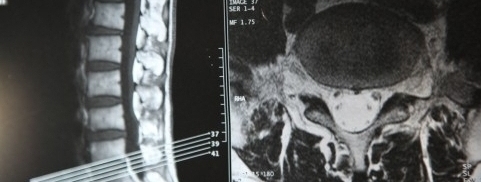

最先端医療器具、医療知識を基に

各検査で身体細部まで状態を調べます。